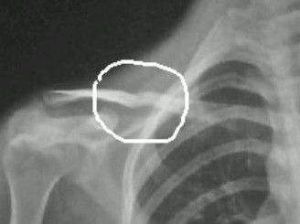

鎖骨骨折是常見上肢骨折之一。《醫宗金鑒•正骨心法要旨》中說:“鎖子骨,經名柱骨,橫臥於兩肩前缺盆之外,其兩端外接肩胛。”鎖骨細長,部位表淺,易受暴力而發...

病因 臨床表現 檢查 診斷 治療鎖骨(clavicle)亦稱“鎖子骨”,是爬行動物、鳥類和哺乳類動物肩胛帶三骨之一。硬骨魚身上已經有其痕跡,有尾兩棲動物仍沒有鎖骨,無尾兩棲動物有鎖骨。...